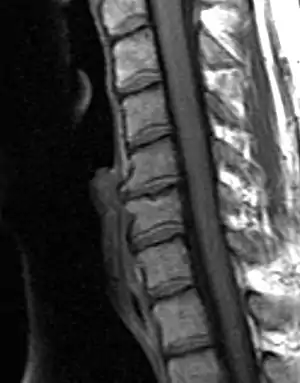

Spinal Arthritis

Degenerative changes observed on the intervertebral joints are not considered osteoarthritis (OA) strictly speaking, since OA only affects synovial joints, whereas intervertebral joints are amphiarthrodial, i.e. cartilaginous joints that allow for mild or minimal movement of the articulating elements.[14] Nonetheless, osteoarthritis and spinal arthritis have a very similar manifestation and they are often grouped together in the bioarchaeological literature. Bioarchaeological and clinical studies have demonstrated that the manifestation of spinal arthritis is linked to factors such as age, sex, body size, mechanical stress, bipedal posture, and others.[15] As with OA, spinal arthritis has been traditionally used in bioarchaeological studies to explore different aspects of social and cultural parameters.

Lesley Gregoricka and Jaime Ullinger from the Ohio State University examined the changes in spinal degenerative disease frequencies of the cervical vertebrae from the Early Bronze Age (3150 – 2300 c. BCE) skeletal assemblage of Bab edh-Dhra’ in Jordan. The aim of the study was to confirm or refute whether an increase in sedentism at the site led to declining workloads. Analysis revealed that the frequency of spinal arthritis decreased from 21% to 13% across the Early Bronze Age at the site. This decrease over time was attributed to a reduction in physical stress on the neck resulting from changes associated with carrying loads on the head. Both authors go on to suggest that the semi-sedentary group of the EB IA (3150 – 3050 c. BCE) were probably practicing small-scale horticulture, yet leaving no significant archaeological remains behind; while the later sedentary group of the Early Bronze Age II-III (2900 – 2300 BCE) at Bab edh-Dhra’ lived year-round next to agricultural fields and streams, therefore, travelling shorter distances for transporting crops and water.[16]